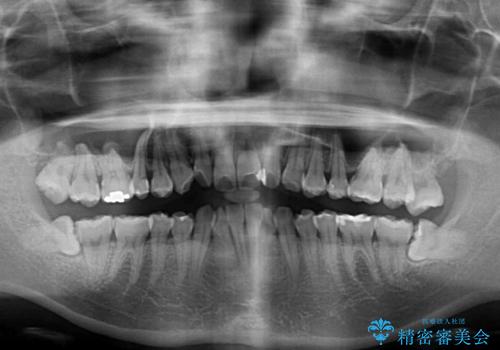

- 上下の前歯のでこぼこを気にして来院された患者様です。

職場の都合により、表側のワイヤー装置や着脱作業が頻繁なマウスピース矯正は困難とのことで、全く目立たない裏側矯正装置を用いて口元を整えることとしました。

途中転勤や出産があり、通院できない期間が長くありましたが、無事に歯列を整えることができました。